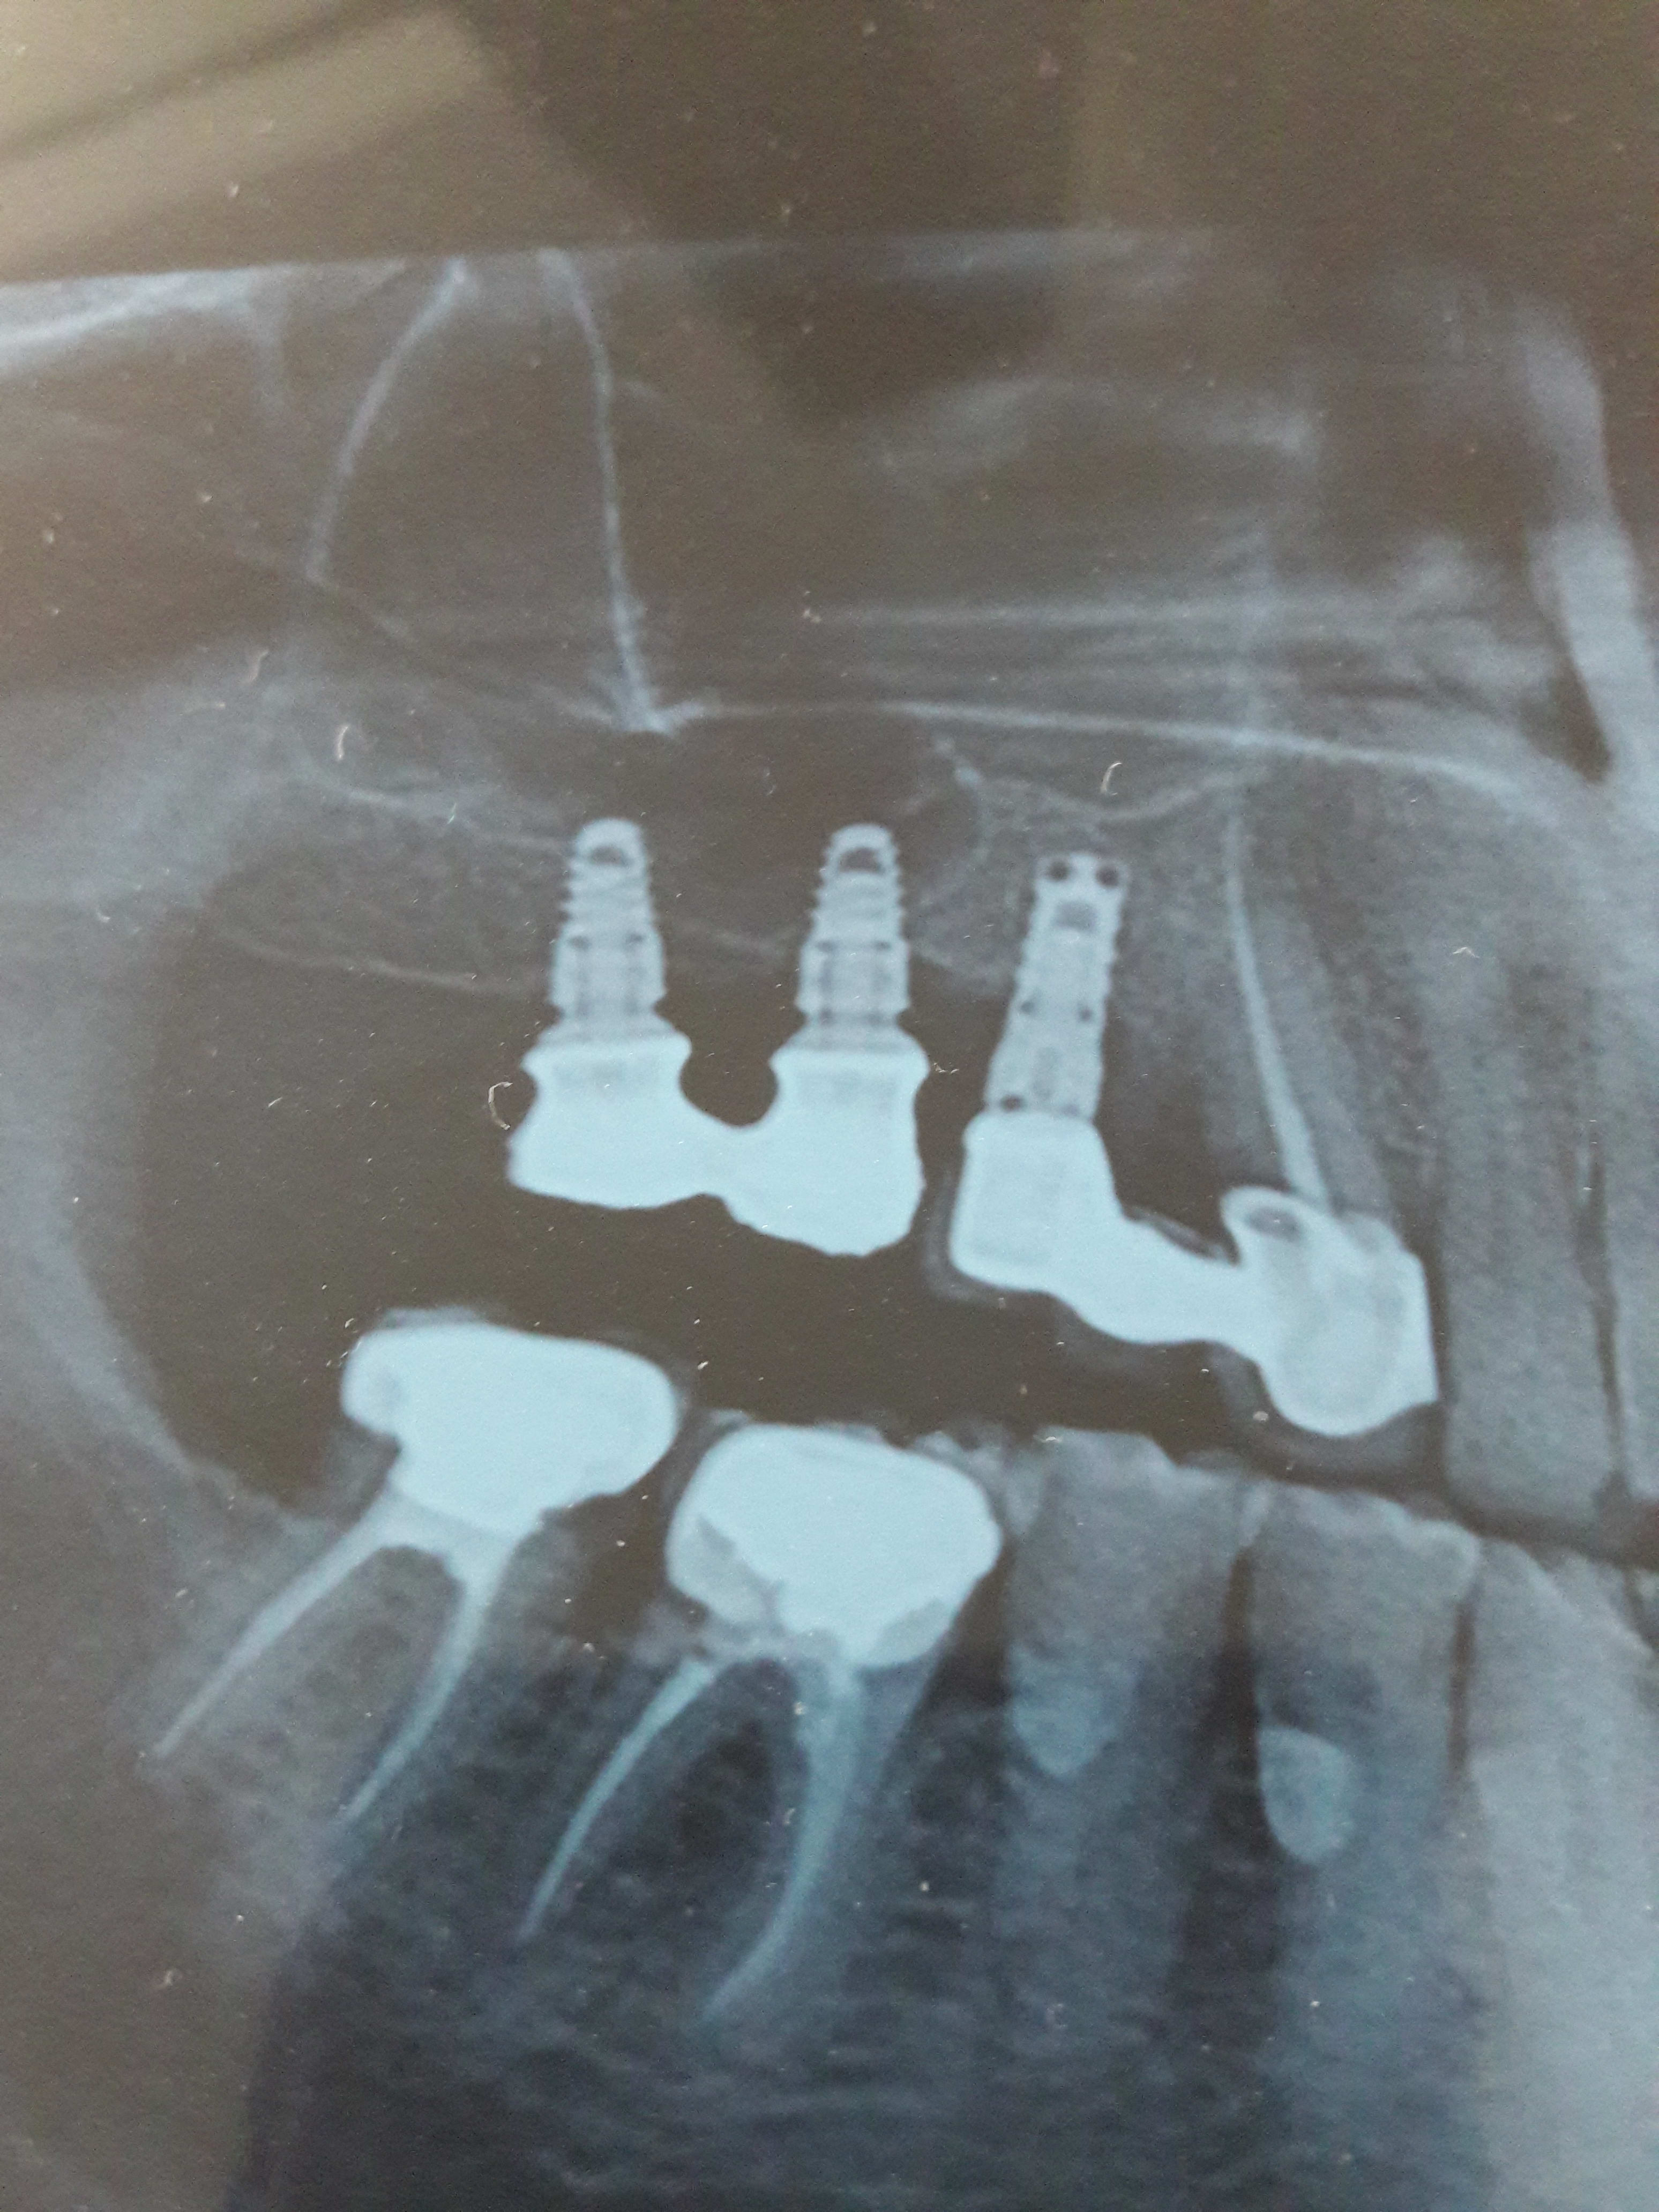

A mon tour, sur 16 et 17, je sais que c'est eurotechnica natural diamètre 4 mais je n'ai pas pu avoir de réponse pour 15 . le patient a des eurotechnica en 26 et 27 également posés par la même personne .

Alors , une idée pour 15 ?

je pense à du TBR pour la 15

oui, TBR

En tout cas, vous êtes trop forts : j'ai pu contacter le poseur maintenant à la retraite qui m'a confirmé que c'est un TBR .Il va regarder dans ses carnets et me dire lequel .

L'implant c'est apparemment un "oct In" mais il ne retrouve pas le diamètre; un 3.5 ou un 4 .

J'ai appelé TBR du coup mais je n'ai pas dù avoir la bonne personne , si besoin j'appellerai le numéro donné par doc . Il ont une hotline pour aider à l'identification de l'implant : j'ai envoyé les radios mais pas de nouvelle pour le moment.

Le tournevis, c'est bien un hexagonal 1.2 ?

tbr c'est un hex plus petit 1mm